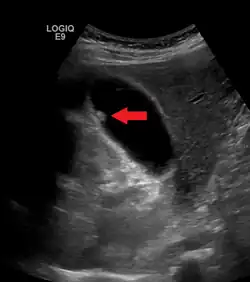

| A polyp in the gall bladder as seen on ultrasound |

Diagnosis is typically by ultrasound or CT imaging.

Ultrasound image of gallbladder polyps measuring 3–7 mm. -